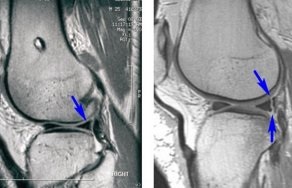

Deteriorarea meniscul în articulația genunchiului - o boală foarte frecvente. Aceasta boala sportivi predispuse și oameni, lucrătorilor cu privire la activitatea fizică. Deteriorarea meniscului sunt cartilajului decalaj. leziuni genunchi sunt separate.

prejudiciu Menisc ocupă primul loc printre cele mai frecvente leziuni ale articulației genunchiului.

Leziunile pot implica regiunea exterioară și interioară a meniscului. Cel mai adesea astfel de leziuni apar la barbati, in special sportivi.

prejudiciu Menisc poate parea marja, sparge posterioare sau anterioare coarne mezhmeniskovyh ruptura de ligamente.

Pentru orice prejudiciu menisc durere caracteristică a spațiului comun, apariția efuziune și limitarea mișcării. În acest context, se poate dezvolta gonartroză.